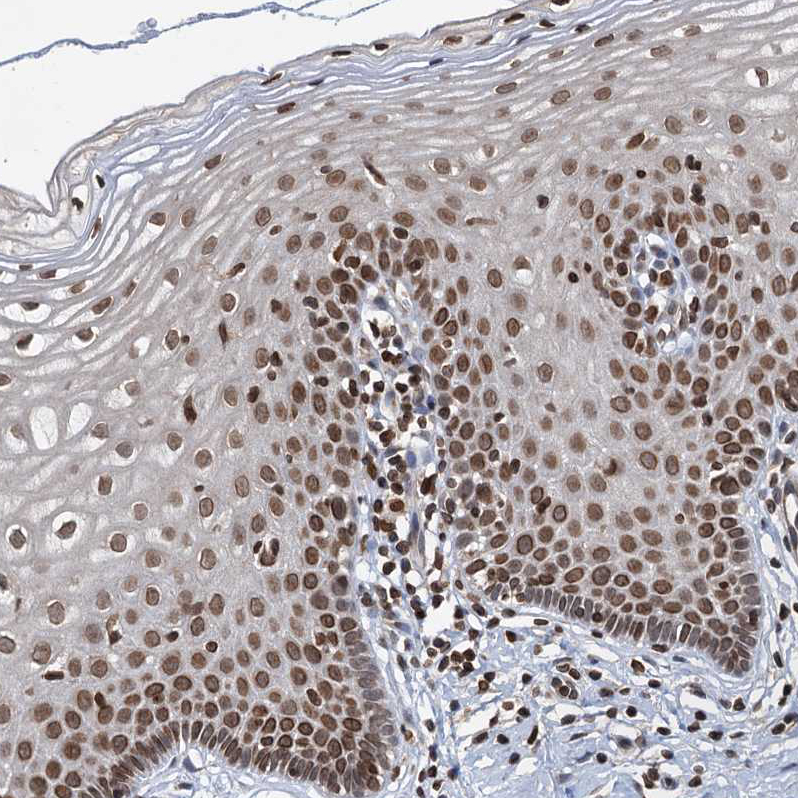

Immunohistochemical staining of human endometrium shows strong nuclear positivity in glandular cells.